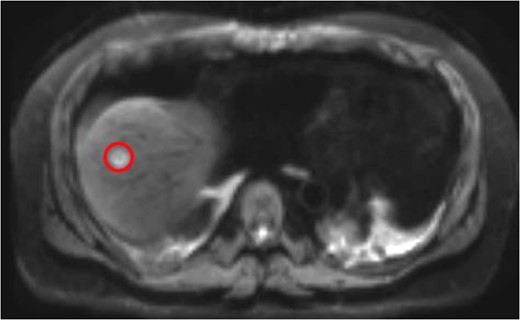

Colonoscopy revealed inflammatory polyps and an ulcerated circumferential mass 30 cm from the anal verge and positive for SCC. Positron emission tomography/computed tomography showed radiotracer uptake in the colon anastomosis, transverse colon, inferior mesenteric artery stump and mesenteric lymph nodes (Figure 1). A 2-cm liver segment VIII lesion was positive for SCC on core needle biopsy (Figure 2).

Liver Metastasis. The red circle indicates the 2-cm site of metastasis.